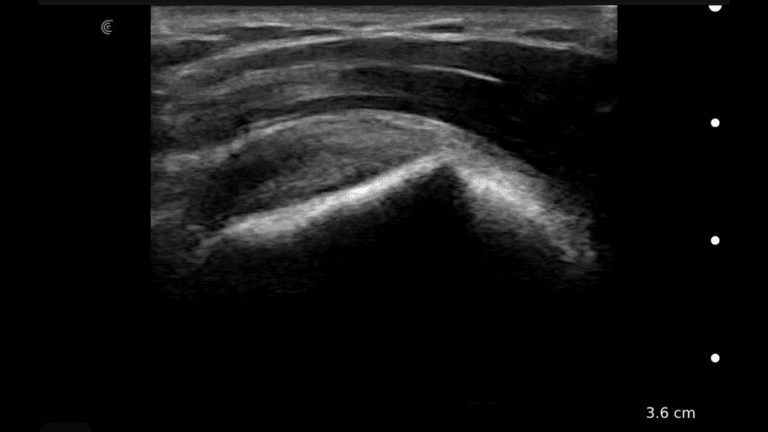

A survey scan of the elbow can identify some of the most common pathologies that cause acute and chronic elbow pain such as tendinosis of the common flexor or extensor tendons, joint effusion, or olecranon bursitis.